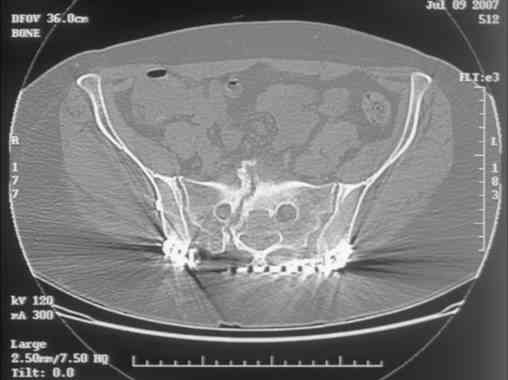

Re: Sacral Non-Union

David Zamorano 25 Август 2007, 21:05

Here is a magnified view. Sorry about the quality but the CT was scanned into our system.

dave

Отправитель: Chip Routt 25 Август 2007, 21:08

Thank you...it might help to remove the disengaged and other iliosacral screws then insert longer lag screws into the upper sacral segment and if anatomically feasible into the second sacral segment as well.

You could do it percutaneously and even add an electrical stimulation device if that seems reasonable.

At this point, I'd ignore the right pubic root issue if asymptomatic.

If simple measures such as those above fail, then you could remove it all, take down the sacral fracture site, refix with alternate techniques, and bone graft.

Chip